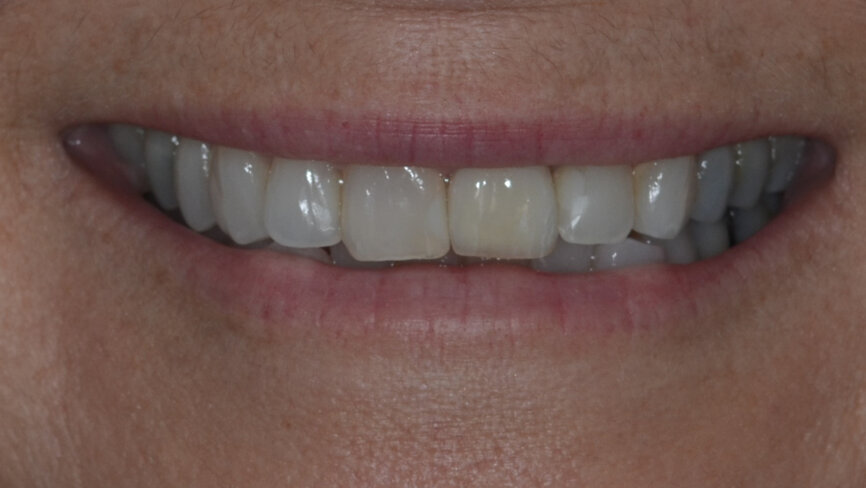

Fig. 31: Final result while smiling.

The final prosthesis was designed using Straumann CARES Visual following a digital workflow. During the design step, it was possible to see that the screw access hole would stay completely to the palatal side with no interference in the aesthetics of the restoration. A monolithic ceramic crown (Prettau Zirconia, Zirkonzahn) was milled and cemented extra-orally to a regular base/wide base Variobase (Straumann) with a gingival height of 1.5 mm, corresponding to the healing remodelling of the bone architecture (Fig. 30). The restoration was seated and screwed to a torque of 25 Ncm after occlusion, contact points and excursive movements had been checked (Figs. 31–33).